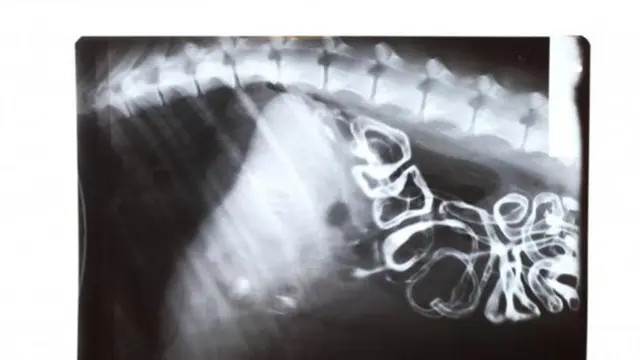

Kanker usus besar

Salah satu hal yang menjadi ciri kanker usus besar adalah pendarahan ketika buang air besar. Namun tak semua buang air besar adalah tanda kalau Anda atau para pria terjangkit penyakit ini.

Kanker jenis ini kerap menyerang pria yang berusia 50 tahun ke atas. Meskipun begitu, kanker usus besar ini dipengaruhi oleh gaya hidup dan pola makan si pria saat masih muda. Zat-zat yang bisa memicu kanker menumpuk dari hari ke hari, dan kanker usus besar semakin menjadi saat sang pria di usia senja.